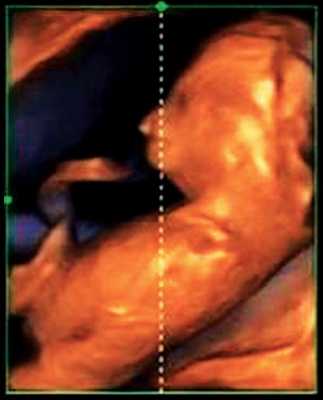

Беременная А., 32 лет. Данная беременность 3-я, в анамнезе 1 неосложненные роды в срок и 1 артифициальный аборт. Наследственность не отягощена. Мужу 36 лет, здоров. Брак не родственный, супруги производственных вредностей не имеют. Пациентка при сроке гестации 13 недель 3 дня обратилась для проведения скрининговой эхографии в городской перинатальный центр (Ростов-на-Дону). Биохимический скрининг I триместра не проводился. Исследование выполнялось на ультразвуковом сканере с использованием режима поверхностной объемной реконструкции 3D/4D.

При эхографии в срок 13 недель 3 дня фетометрические параметры плода соответствовали гестационной норме, толщина воротникового пространства составила 1,5 мм; длина костей носа - по 2,5 мм. При трансвагинальном сканировании были обнаружены: затылочное энцефалоцеле размерами 7,4х3,5х3,7 мм (рис. 1), полидактилия кистей (рис. 2), увеличенные кистозно-измененные почки: правая - 28,5х21,3 мм; левая - 26,4х18,7 мм (рис. 3). Объем амниотической полости был нормальным для данного срока.